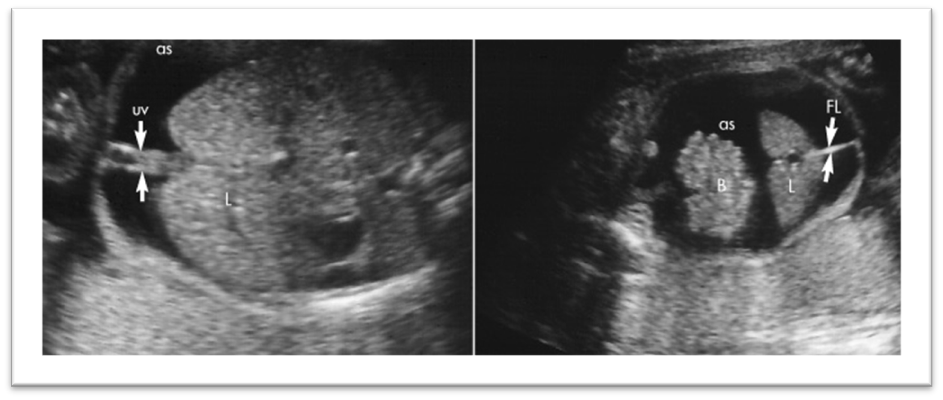

What are these images showing?

Duodenal Atresia

Bowel Obstruction